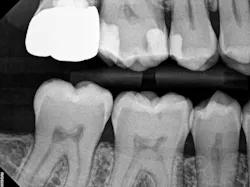

In the case below, tooth No. 2 was diagnosed with symptomatic irreversible pulpitis and symptomatic apical periodontitis with a mesial marginal ridge fracture due to extensive caries (figure 1). Root canal therapy and a full coverage crown were recommended and the patient accepted.